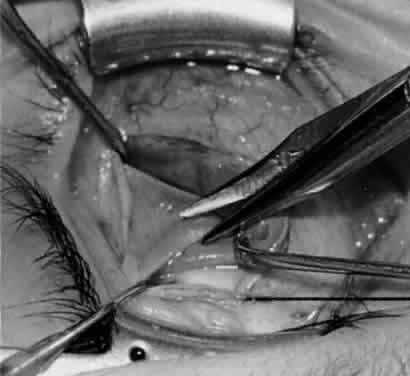

Fig. 5. The Stevens hook is placed adjacent to the posterior edge of the inferior oblique muscle and rotated as the inferior oblique muscle is drawn into the operative field. A forceps is used to retract the redundant Tenon's capsule, encapsulated fat, and intermuscular septum as the muscle is drawn further into the operative field with the Stevens muscle hook.

Fig. 6. The Westcott scissor is used to open the intermuscular septum along the posterior border of the inferior oblique muscle. Care is taken to cut adjacent to the tip of the Stevens muscle hook. This incision is important because it helps to avoid damaging the Tenon's capsule and releasing fat, which leads to the adherence syndrome and postoperative hypotropia.

Fig. 7. A Westcott scissor is used gently to open a space beneath the elevated inferior oblique muscle and allow placement of a Green muscle hook.

Fig. 8. The Green muscle hook is placed beneath the belly of the inferior oblique muscle, and the eye is retracted nasally.